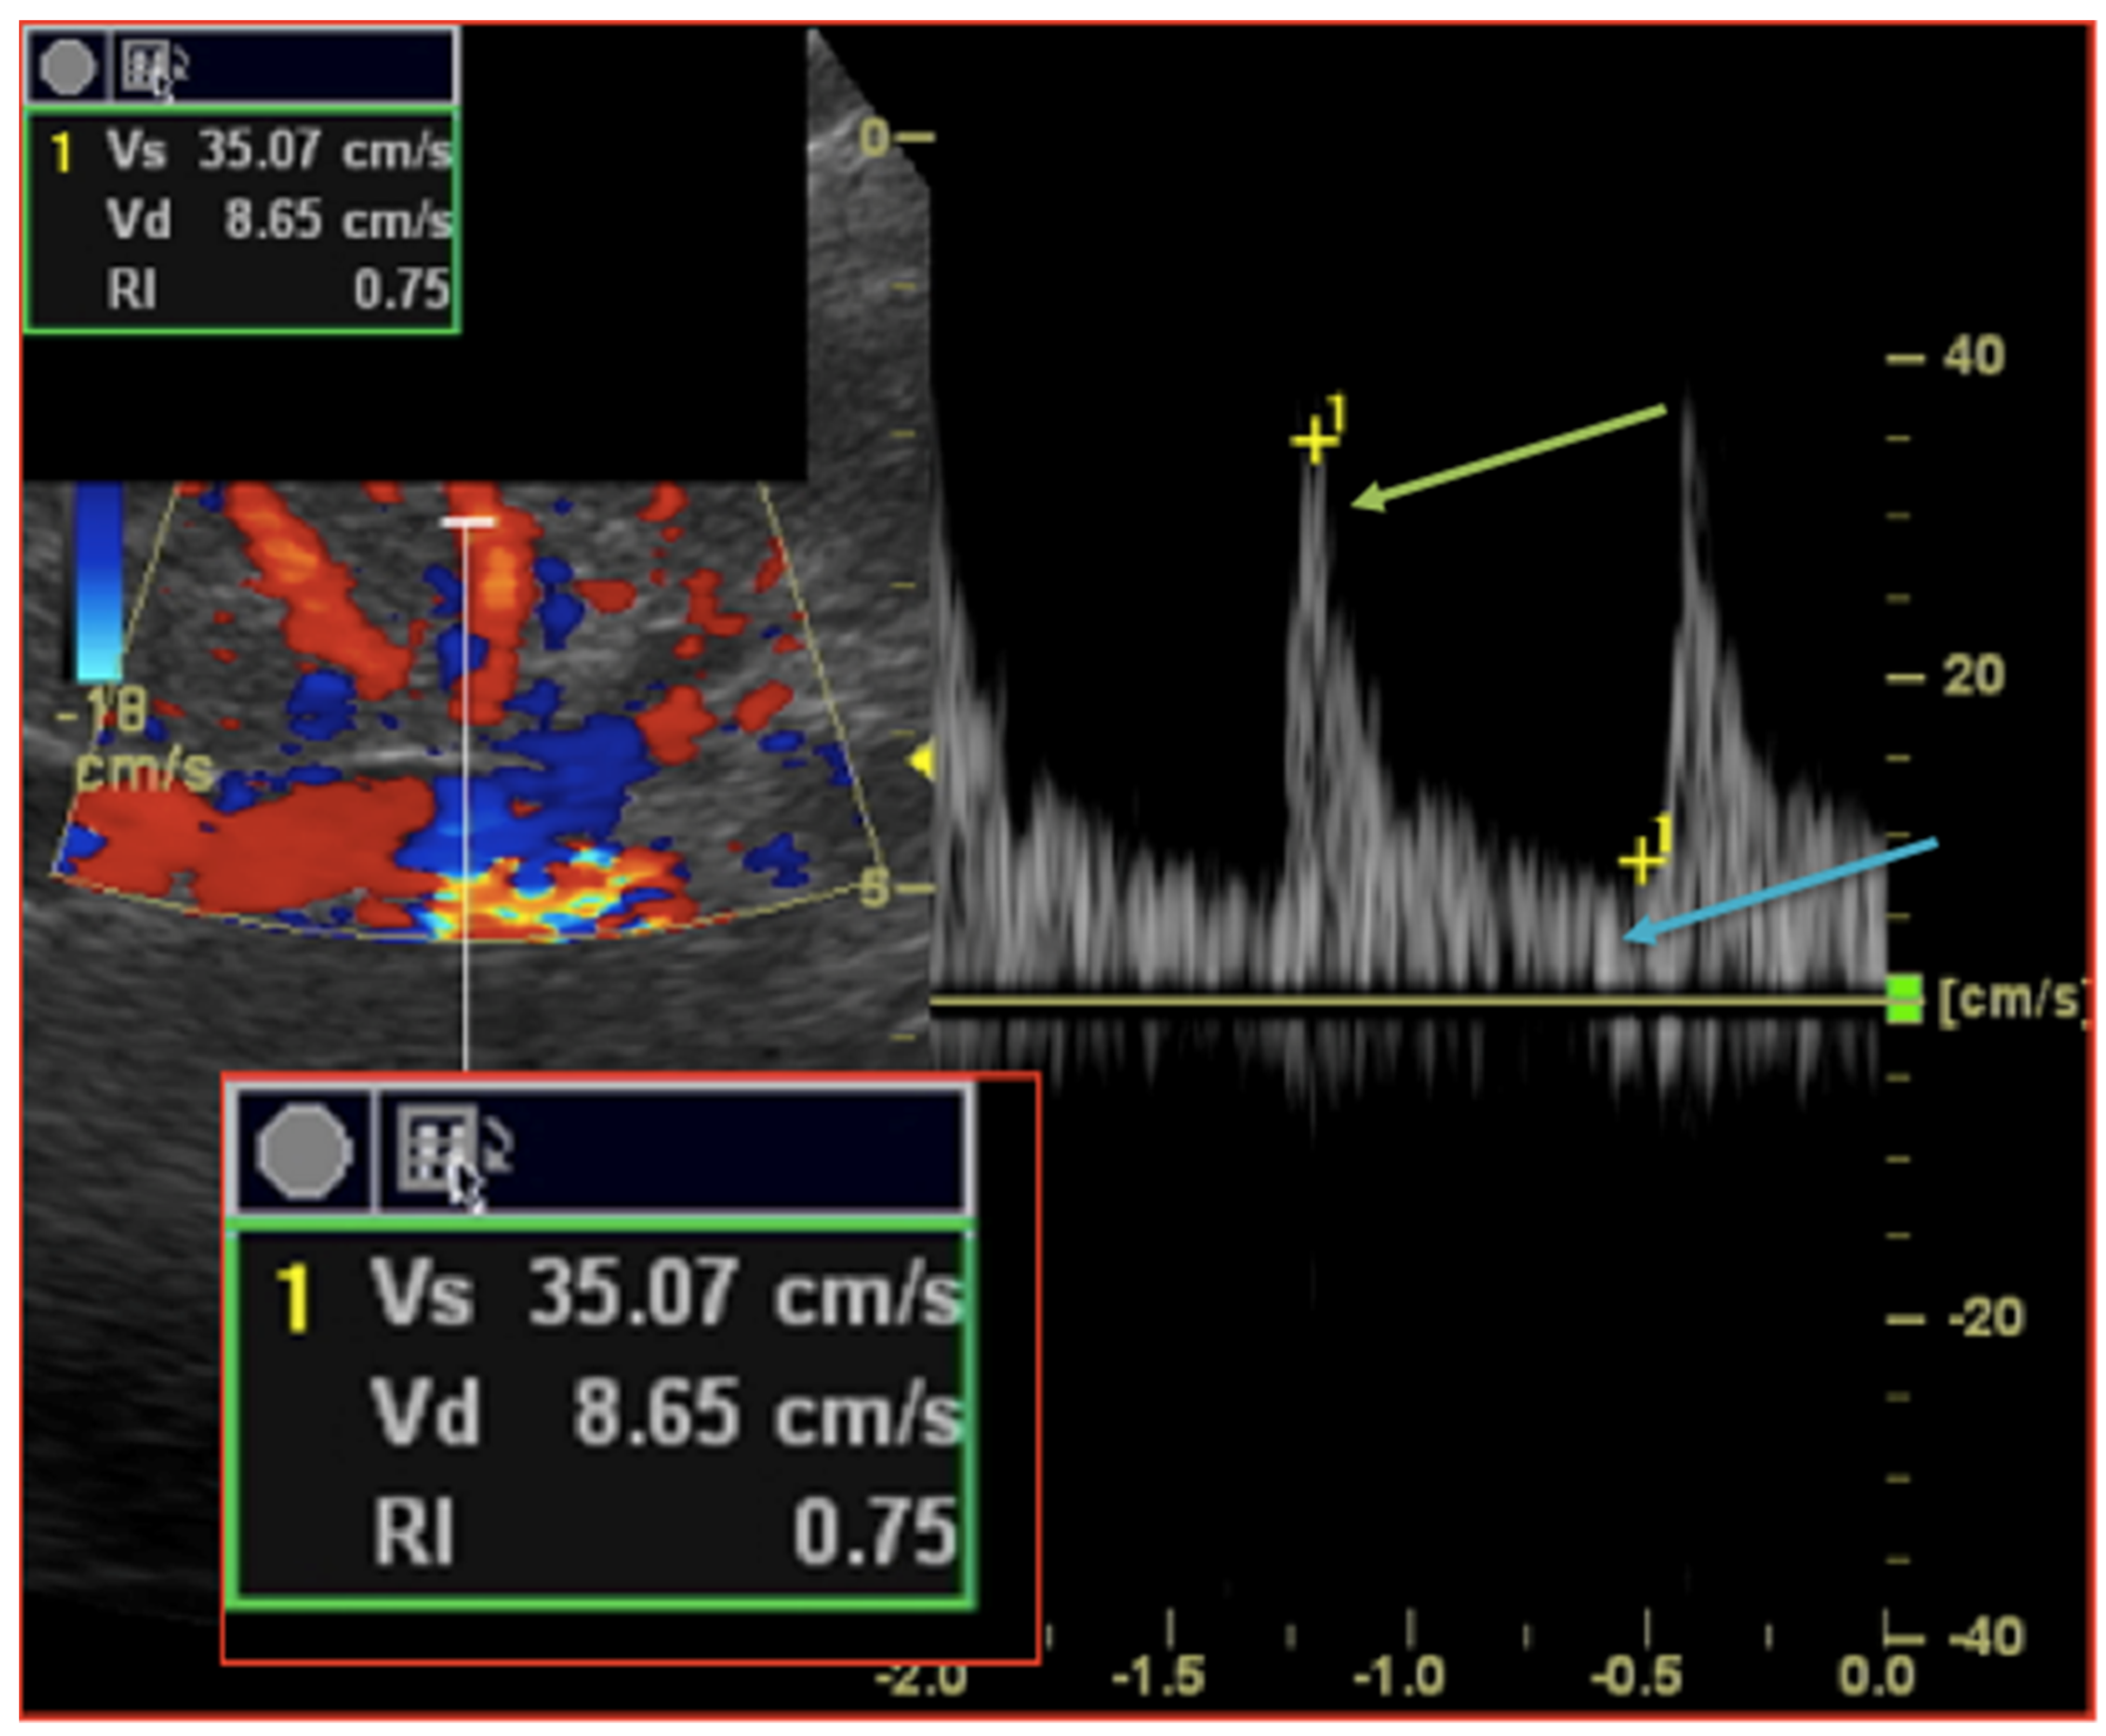

Patients with previous known renal artery disease (renal artery stenosis, occlusion or renal artery/vein thrombosis) were excluded from further analysis. RDU measurements were performed 12 h prior, 24 h and 72 h after TAVR procedures. According to previous work and validated methodology, renal resistive index (RRI) was measured with an ultrasound-Doppler pulsed-wave Doppler probe (5S ultrasound transducer, General Electric Medical Systems) on a Vivid S7 ultrasound system by two independent trained physicians. After locating the kidneys, intrarenal renal vessels were identified using color Doppler and sampling for RRI screened at the level of interlobar arteries. Measurements using pulse-wave Doppler were repeated in different parts (superior, median, and lower) of the kidney and at least three reproducible and consecutive waveforms were obtained to measure RRI parameters (Figure 1). The RRI index was calculated according to the following formula: ((peak systolic velocity − end diastolic velocity)/peak systolic velocity). The mean value of three different measurements was recorded. The mean reference value for normal RRI in adults is 0.60 ± 0.10 and 0.70 considered as the upper limit of normal [,,].

Figure 1. Intrarenal Doppler Ultrasonography: Renal Resistive index measurement technique. A sample volume is placed within an interlobar artery using Colour Doppler guidance. Spectral analysis of vascular signals is then obtained, and measurement callipers are set as follow: (i) systolic peak (green arrow); (ii) end diastole peak (blue arrow). Renal Resistive index is then calculated according to the formula (Vs − Vs)/Vs.